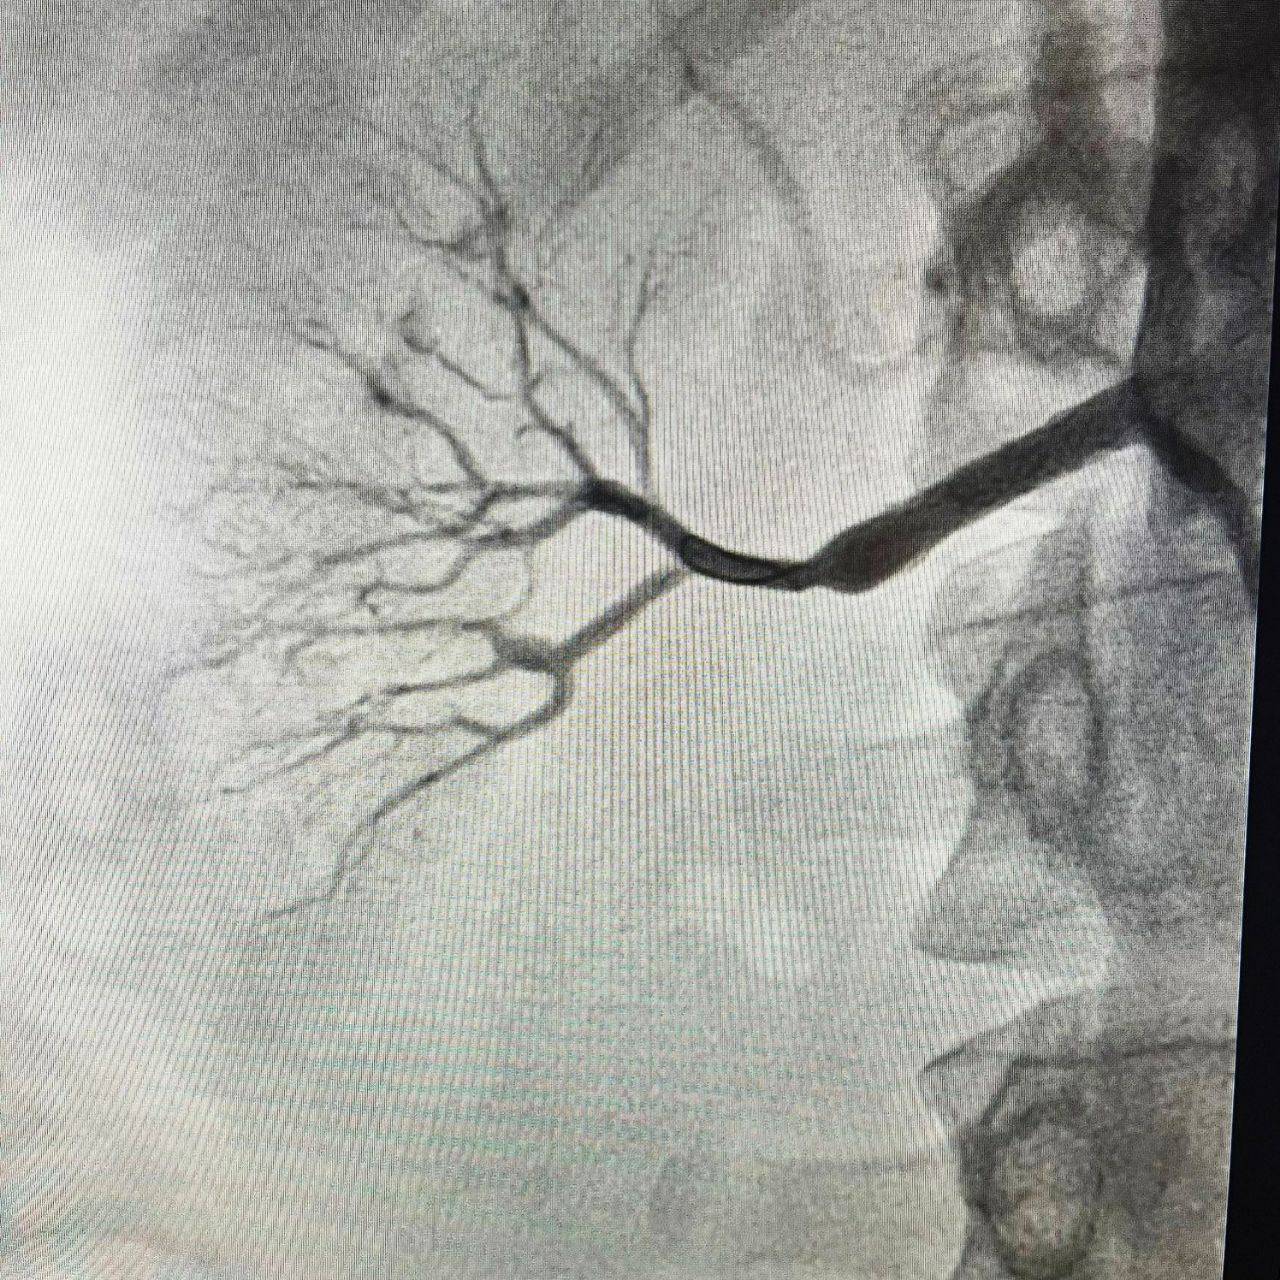

«Это уникальный случай, с которым мы столкнулись впервые. Фиброз практически полностью перекрыл правую почечную артерию. Мы провели углубленную КТ, убедились, что почка сохраняет функцию, и приняли решение срочно оперировать. Без вмешательства орган был обречён», — рассказал рентгенэндоваскулярный хирург ПККБ №1 Вячеслав Воробьёв.

Для операции специалисты заказали индивидуальный стент, способный выдержать высокое давление. Вмешательство выполнил заведующий отделением рентгенохирургических методов диагностики и лечения РСЦ Никита Грачёв. Процедура длилась около получаса и завершилась успешно.